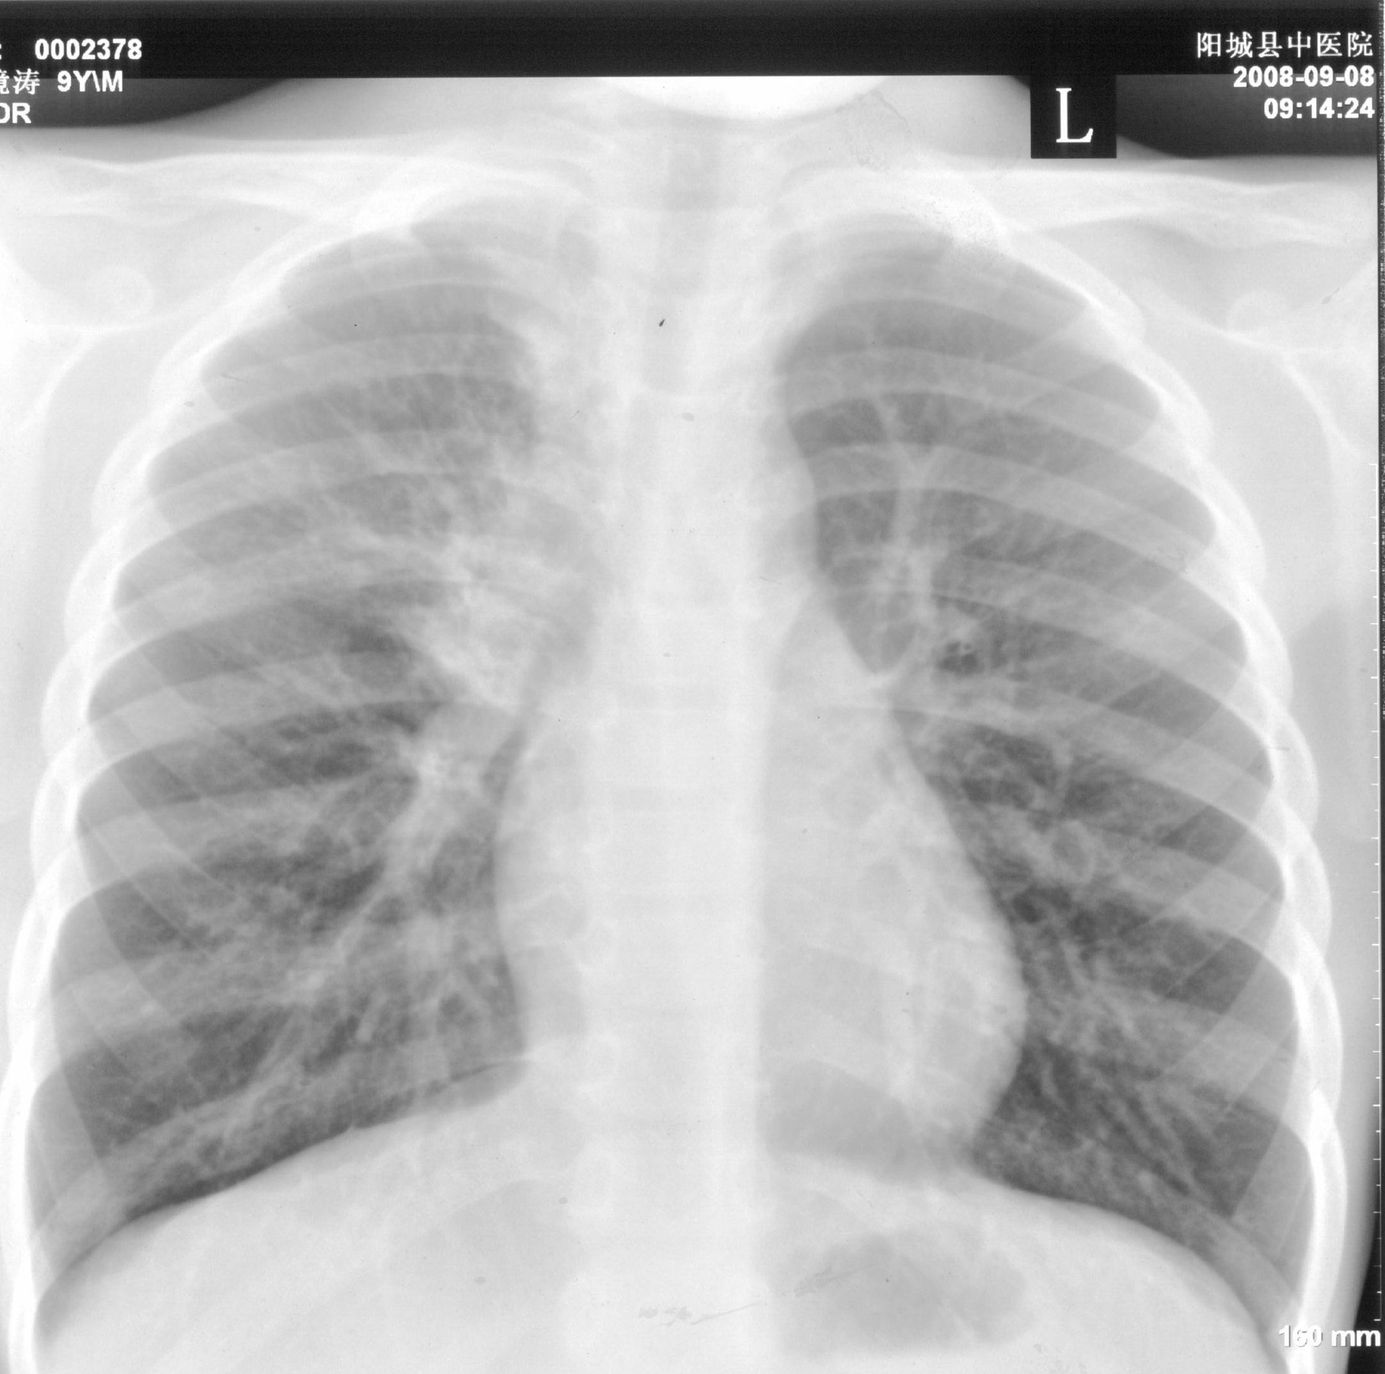

9月15号平片检查情况:

右上肺不均匀密度增高,体积变小,水平裂弧状上移,纵隔内有肿大的淋巴结。考虑:

1、右上肺炎(吸收期),纵隔淋巴结肿大压迫右上叶肺膨张不全

2、纵隔淋巴结结核不能排除

建议继续抗炎治疗短期复查